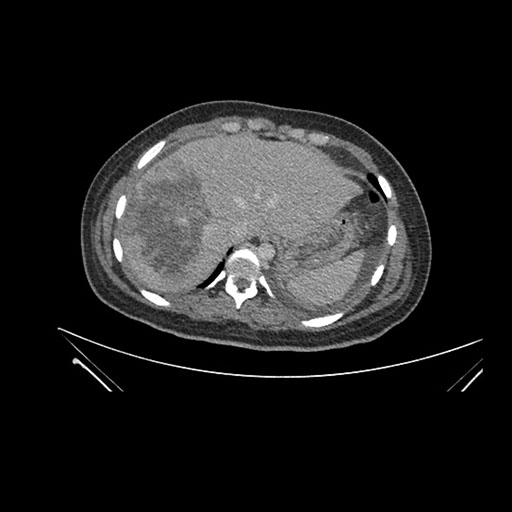

Imaging Analysis

Look through the patient's CT scan to identify any areas of concern for the necessary procedure.

Axial Arterial

Based on initial findings, which issue(s) would you be most concerned about?